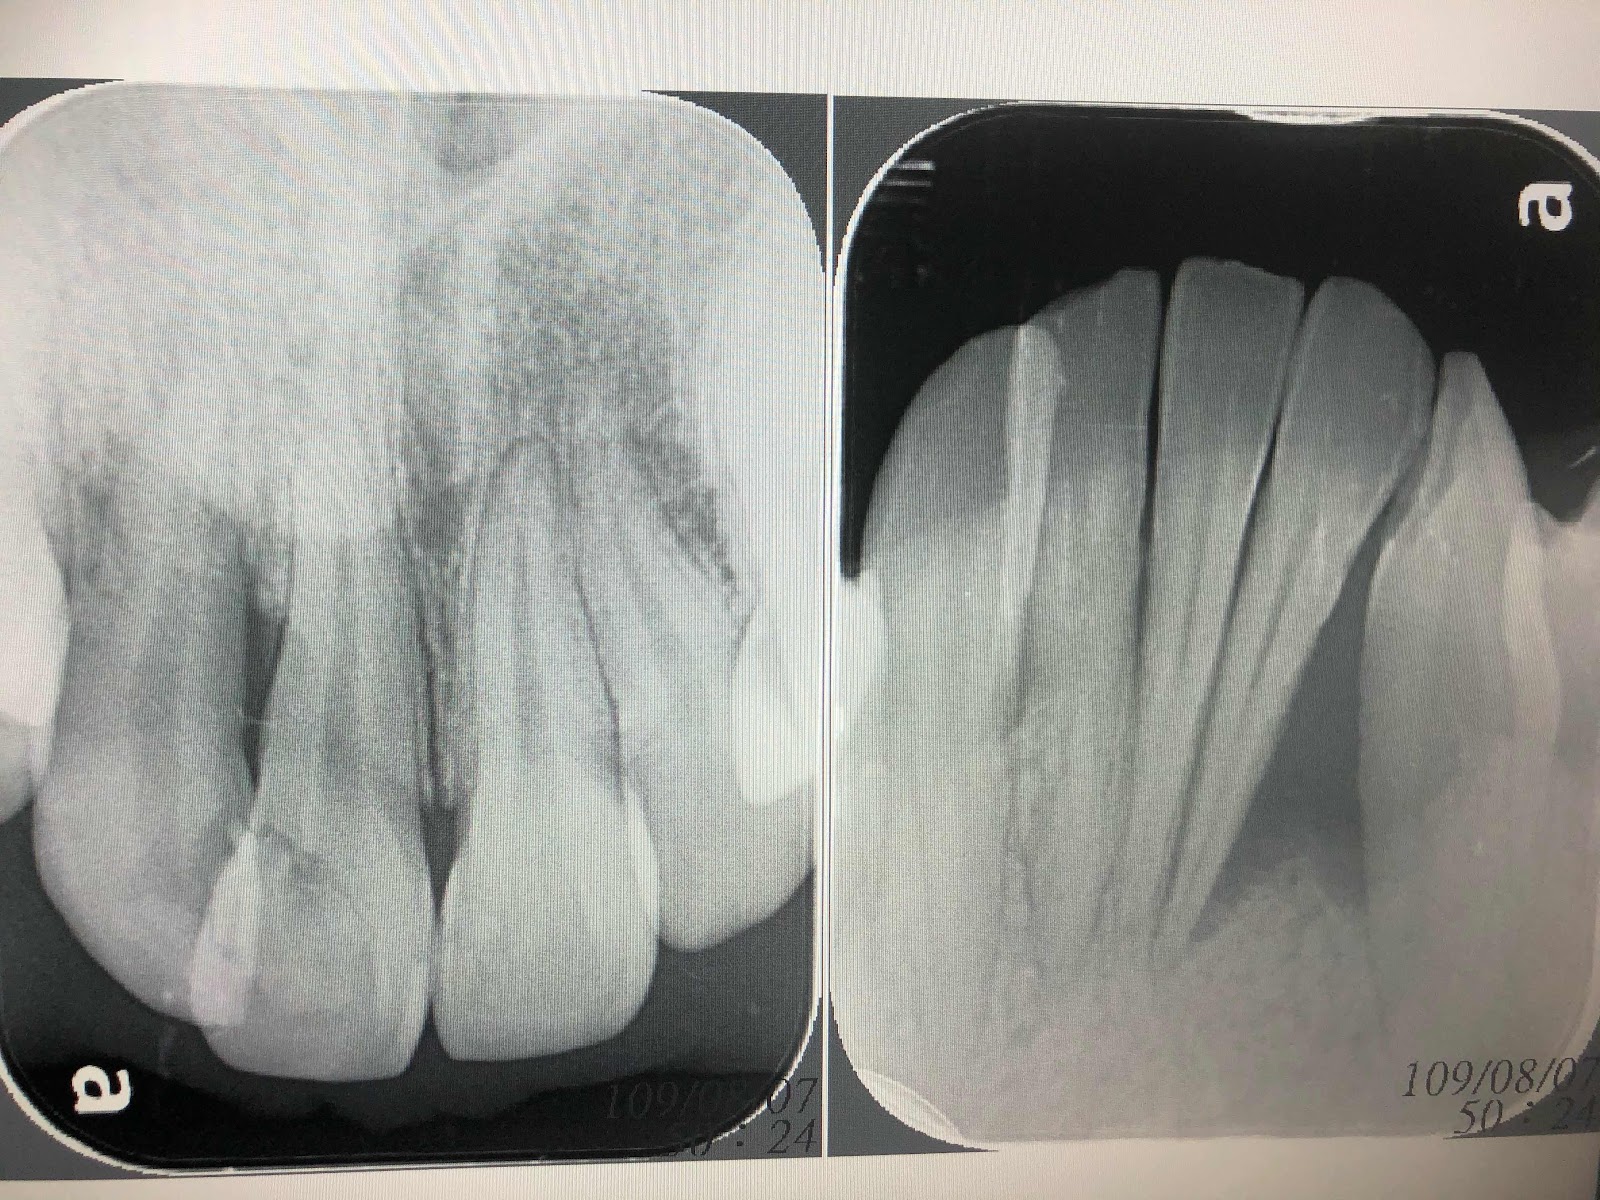

(1)牙周囊袋測量(一顆牙齒分為六個面,三以下為正常、五以上就是有需要處理了)

(2)牙齦下牙結石刮除(將囊袋深度五以上的區域處理)

(3)術後牙周囊袋再測量(結石刮除後等一個月再測量,看治療反應,如果還有五以上,就會建議手術治療)